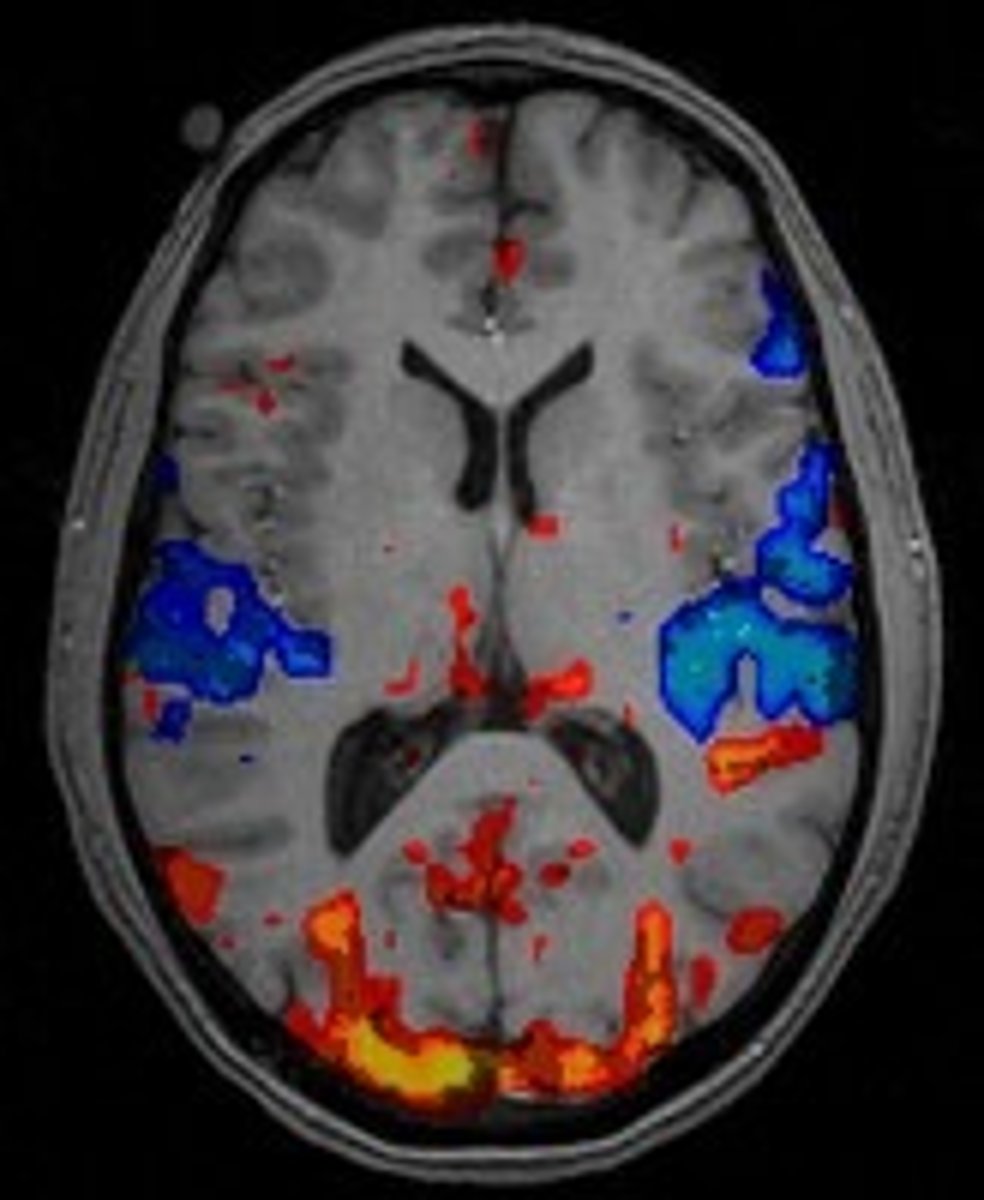

fMRI

Magnetic imaging of the brain which shows which active areas of the brain